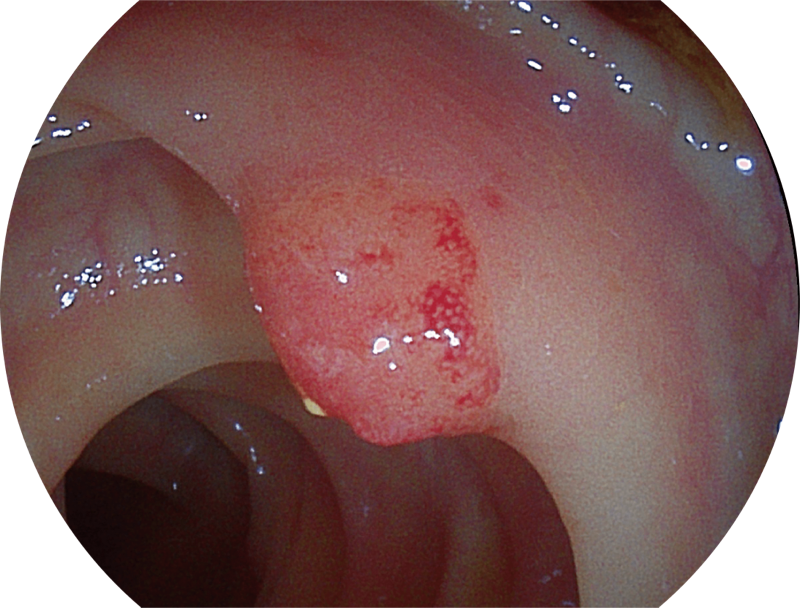

能够凸显黏膜浅层和中层血管轮廓,适用于中、远景观察下的病灶识别和早癌筛查。

能够凸显黏膜浅层血管轮廓和黏膜表面微结构,适用于中、近景观察下的早癌精确诊断。